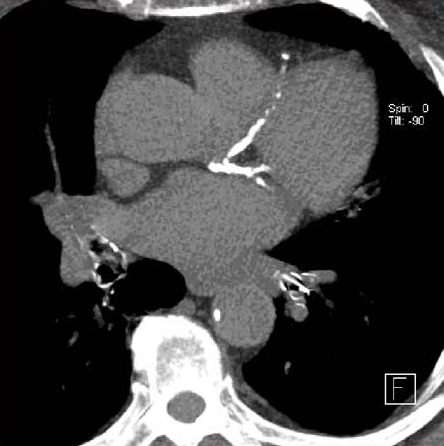

En las personas que se sometieron a una TC de tórax de baja dosis para la detección del cáncer de pulmón, la presencia de calcio en la arteria coronaria fue un predictor independiente de muerte por cualquier causa y eventos cardiovasculares, incluso después del ajuste por muerte no cardiovascular. Canadian Medical Association Journal, 2 de diciembre de 2024.

Un puntaje de 0 en el calcio coronario medido por angiotomografía computada reduce sustancialmente el riesgo de enfermedad coronaria en los adultos mayores, pero en los pacientes más jóvenes se halló que una proporción considerable de la coronariopatía obstructiva ocurre en aquellos sin calcio coronario. JAMA Cardiology, 27 de octubre de 2021.